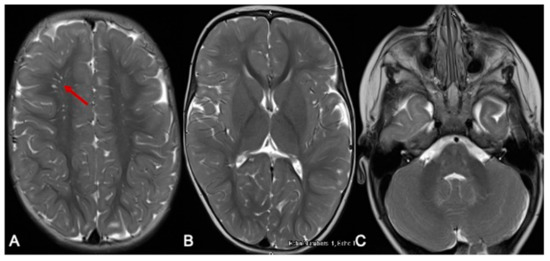

Ammonia was 113 μmol/L (10–50 μmol/L). She commenced intravenous dextrose 10% containing fluids and lipids in the acute setting, oral thiamine supplementation, a protein-restricted diet and MSUD-specific, BCAA-free formula (MSUD Anamix Infant, Nutricia Australia). MRI of the brain demonstrated bilateral symmetrical T2 hyperintense signal changes involving the white matter globus pallidus thalamus brainstem and dentate nuclei with restricted diffusion (Figure 1). EEG was mildly abnormal, with intermittent slowing (2–3 Hz amplitude slowing) noted bilaterally and unilaterally in the posterior and frontal regions with occasional generalised bursts and occasional right centrotemporal sharp transients. She responded well to the dietary intervention and was discharged home with residual neurological sequelae including hypotonia and continued involuntary limb movements, which were assessed to be myoclonic jerks.

Figure 1.

MRI of the brain at 7 months. The red arrows show the hyperintense signal changes. T2-weighted axial images of an MRI scan of the brain at 7 months of age (A–C) show hyperintense signal changes in the white matter (A), globus pallidus (B), and thalamus (B); pons, cerebellar peduncle, and dentate nucleus (C arrows). The corresponding areas show restricted diffusion in DWI Images (D–F) and ADC maps (G–I).